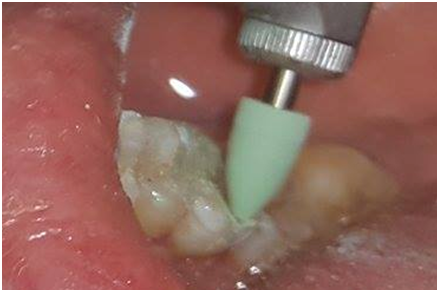

Gross excess resin can be removed after a spot cure, prior to completely curing the resin. Light curing is then done in accordance with the resin manufacturer’s recommendations. Any residual flash can be removed with a scalpel or suitable curette, but care must be taken not to cause inadvertent deficiencies at the tooth restoration interface.2,7 after which the occlusion is evaluated and adjusted as necessary. Any adjusted surfaces can be polished with a suitable polishing system, such as diamond polishing paste or rubber points (Figure 14 & Figure 15).7

Figure 14 Periapical view after bonding.